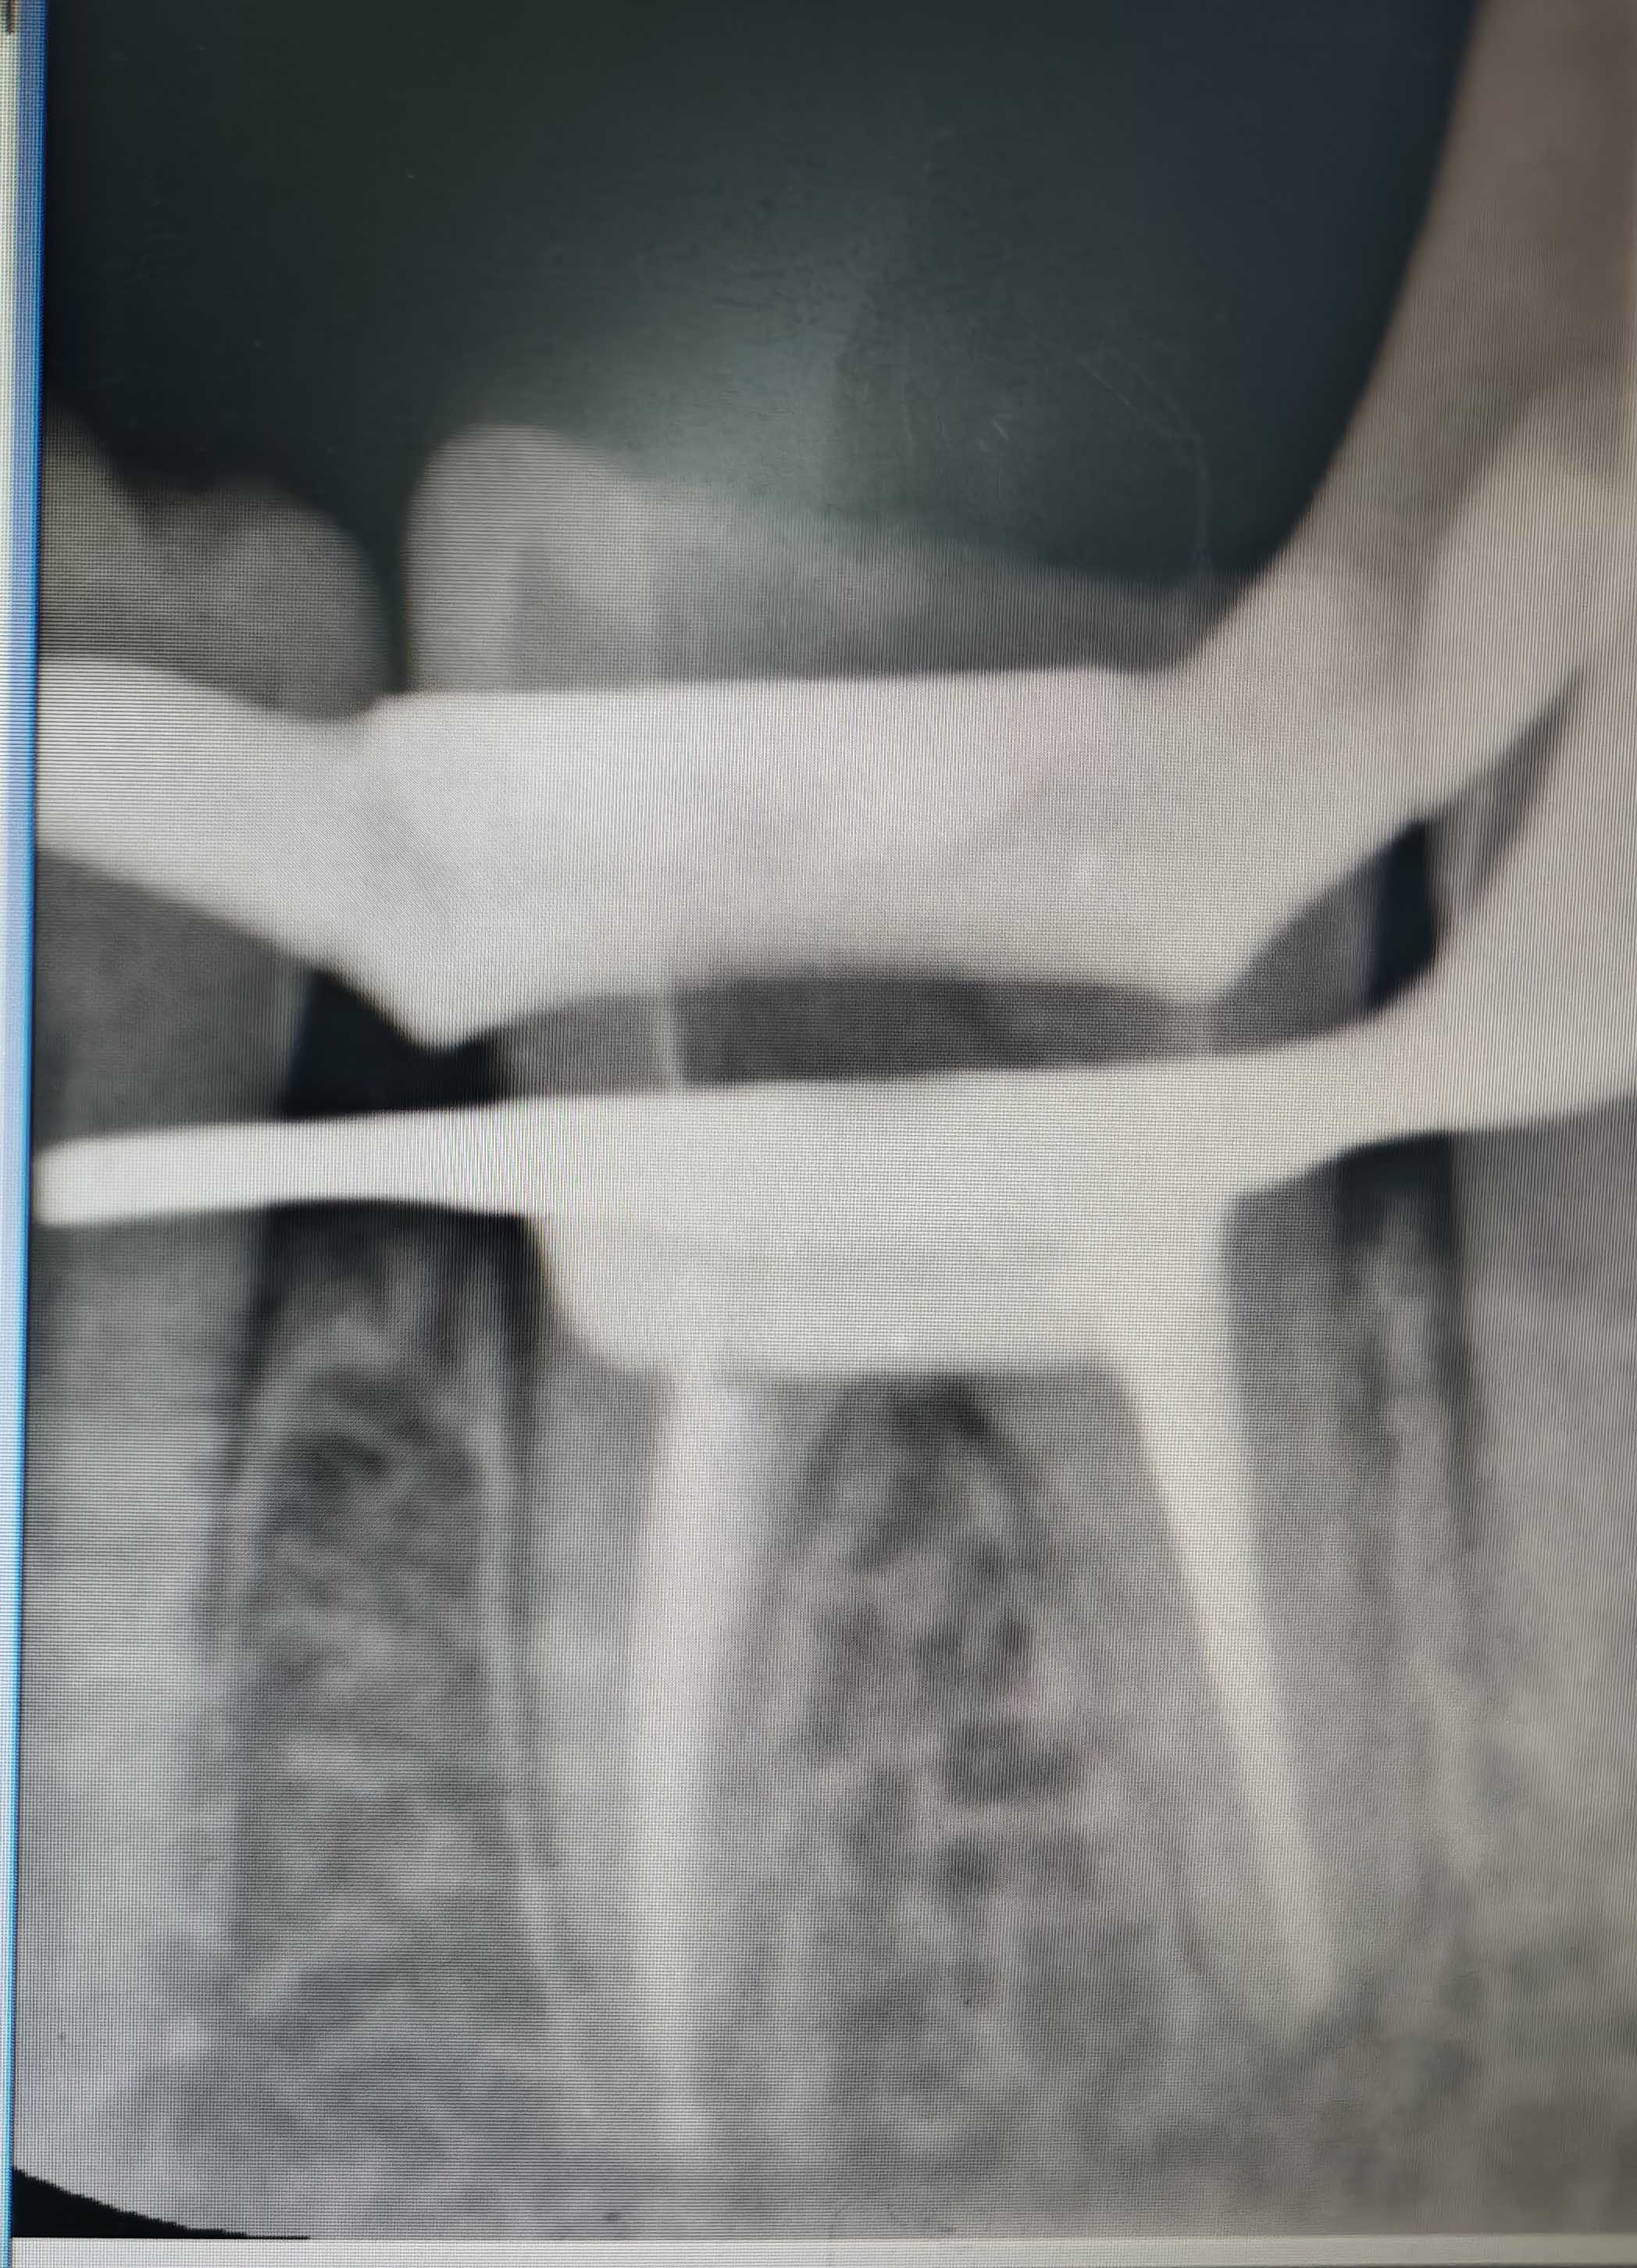

根管治疗

根管治疗 - 案例一

术前 术前

术后 术后